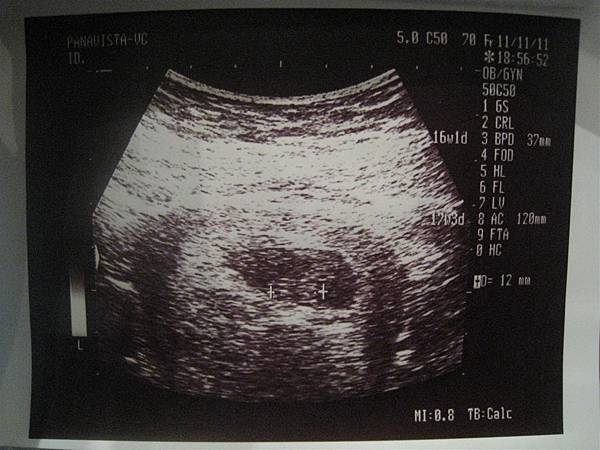

目前蘋果媽剛滿14周,孕程前段的不穩定期已經順順利利的度過了。

預產期原先是101年6月22日,

不過黃光大醫生照超音波之後把預產期往後校正為6月24日。